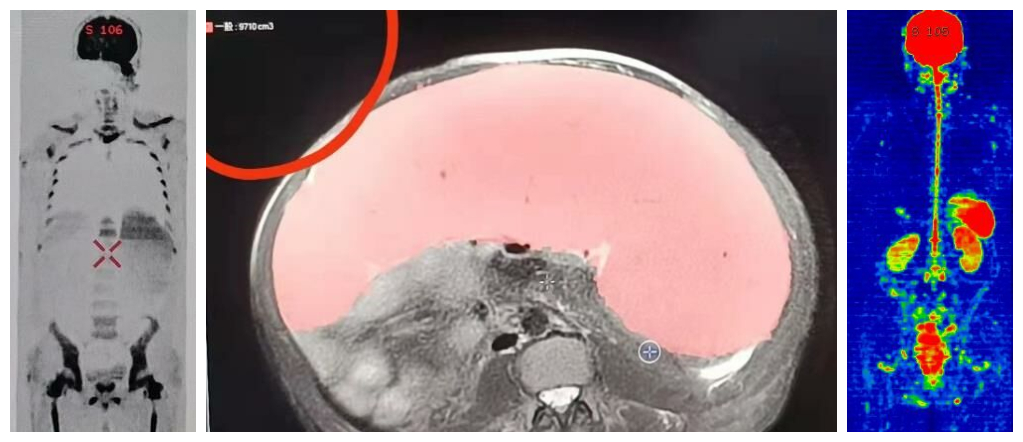

4月:多次和血液科合作探索血液系统基本进行磁共振类PET成像技术,巨脾治疗前后磁共振体积定量评估等(图6)。

图6类PET和磁共振脾体积定量测定